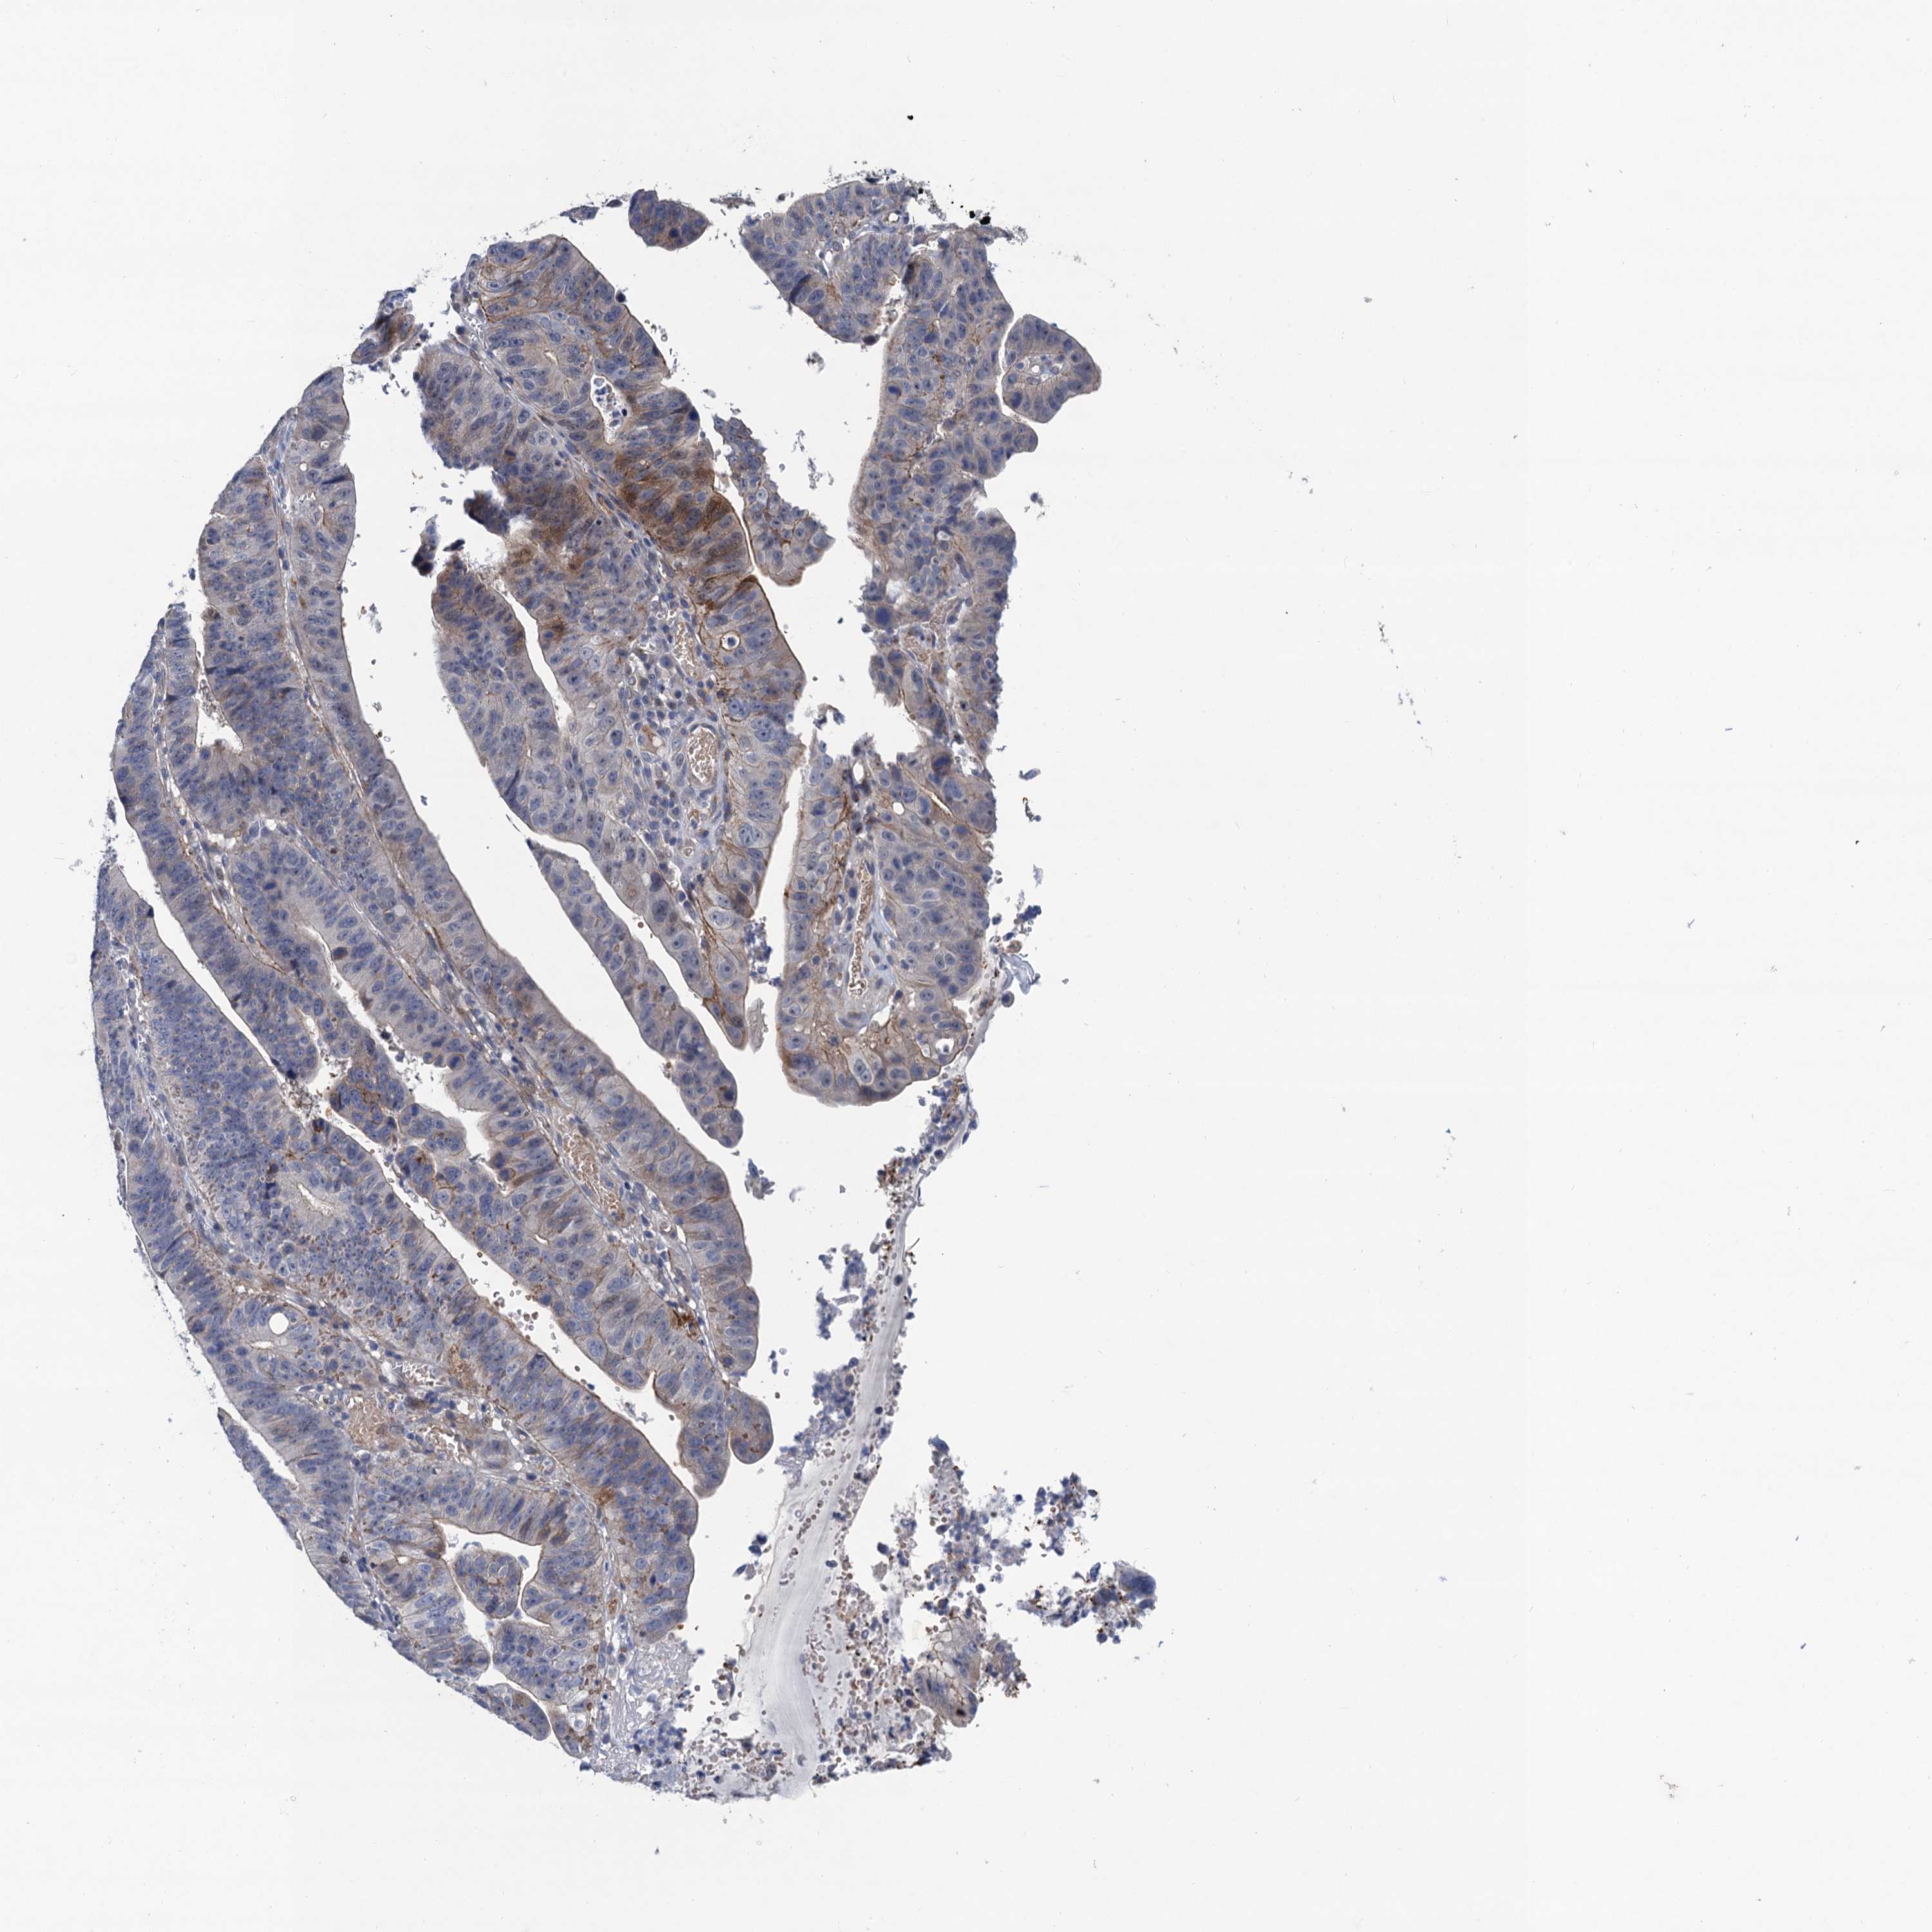

STOMACH CANCER - Protein expressioni

A mouse-over function shows sample information and annotation data. Click on an image to view it in a full screen mode. Samples can be filtered based on level of antibody staining by selecting one or several of the following categories: high, medium, low and not detected. The assay and annotation is described here.

Note that samples used for immunohistochemistry by the Human Protein Atlas do not correspond to samples in the TCGA dataset.

Antibody stainingi

Antibody staining in the annotated cell types in the current human tissue is reported as not detected, low, medium, or high, based on conventional immunohistochemistry profiling in selected tissues. This score is based on the combination of the staining intensity and fraction of stained cells.

Each image is clickable and will lead to virtual microscopy that enables deeper exploration of all samples and also displays staining intensity scores, fraction scores and subcellular localization as well as patient and tissue information for each sample.

Antibody HPA041229

Staining

High

Medium

Low

Not detected

Intensity

Strong

Moderate

Weak

Negative

Quantity

>75%

75%-25%

<25%

None

Location

Nuclear

Cytoplasmic/membranous

Cytoplasmic/membranous,nuclear

Adenocarcinoma, NOS

Adenocarcinoma, High grade